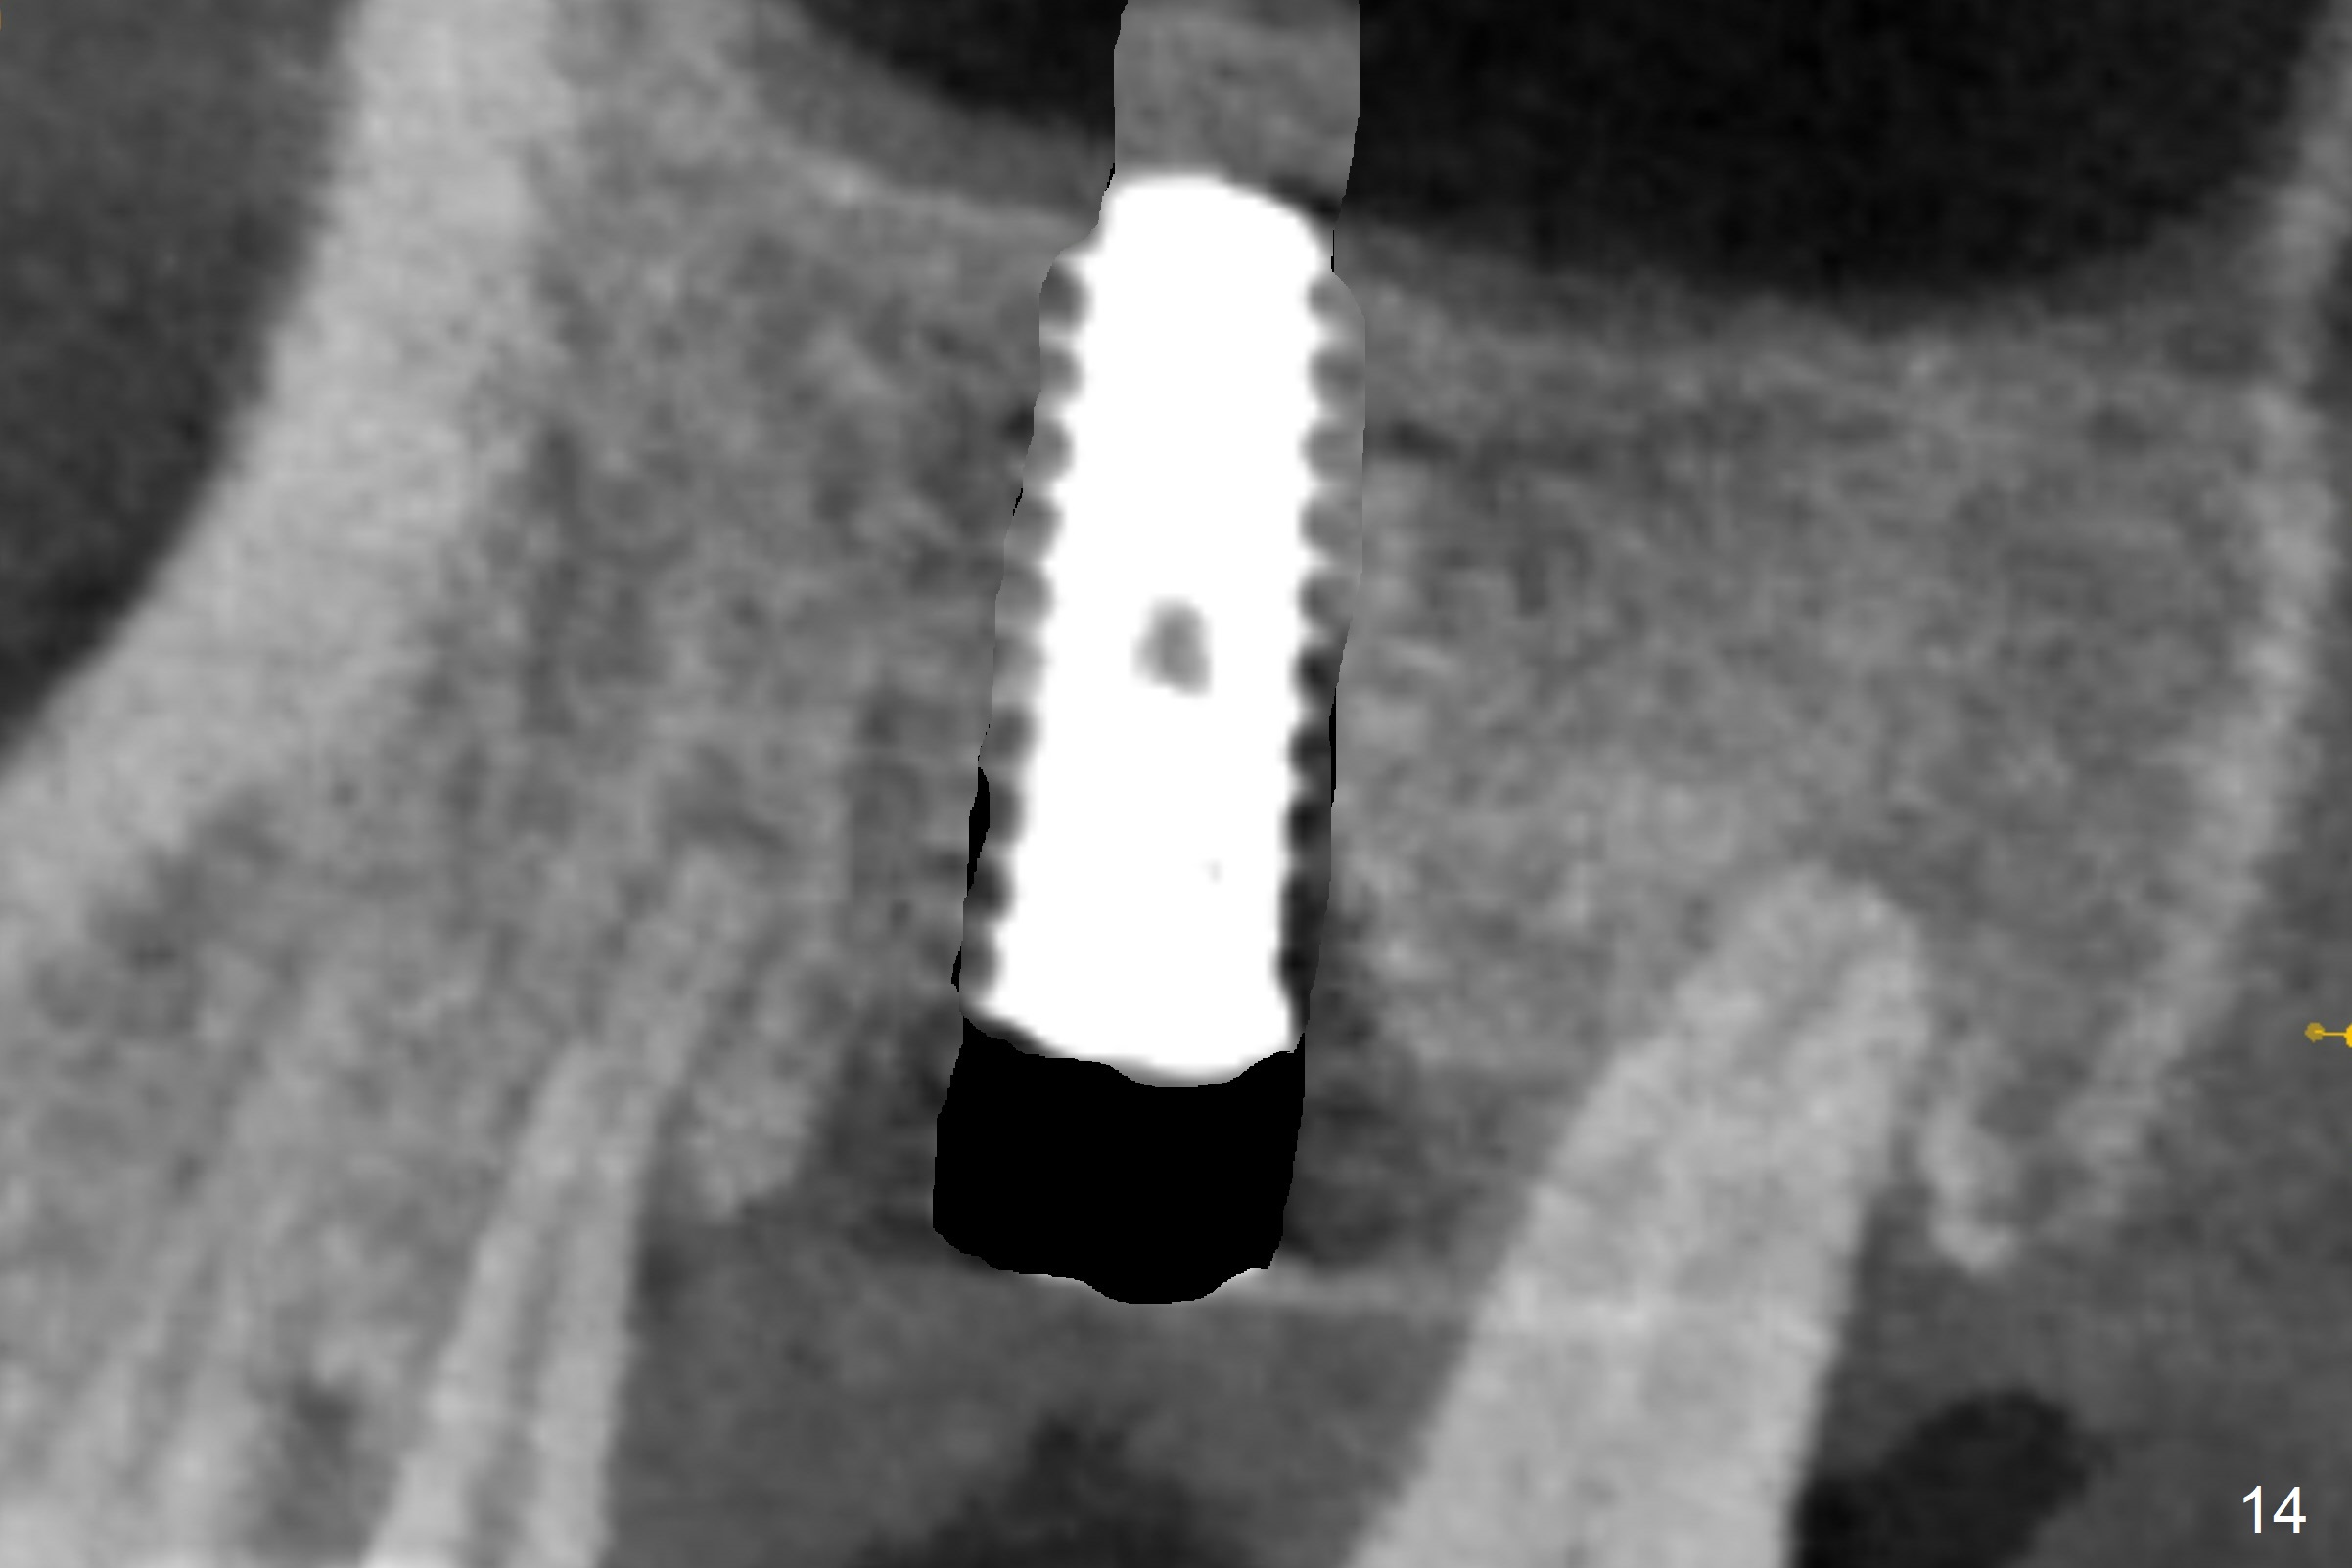

The amount of the bone graft mesial and distal the implant seems to reduce 3 and 4 months postop, respectively (Fig.6,7 arrowheads). When the acrylic is cut off 4 months postop, the bone graft is loose. The gingiva is unhealthy. The abutment and implant are loose. A healing abutment is placed (5x4 mm). The implant is torqued to 35 Ncm 6 months postop with the healing abutment reapplied. The patient will return for follow up nearly 9 months postop. A larger healing abutment will be used if the implant is stable. Two weeks later, use a smaller restorative abutment for easy impression. In fact the implant is unstable with #15 mesial shift due to abnormal occlusion with #17 (Fig.8). Bone density around the implant is low (* in Fig.9 (PA), 10,11 (CT sagittal, coronal sections)). A healing screw is placed for self healing. A 2nd option is to remove the implant (Fig.12), BEB (Fig.13) and place the implant deeper (Fig.14) or larger one (5.5-6.5x13 mm). The 3rd option is to place larger and longer implants (Fig.15 (tapered), 16 (cylindrical)). The implant access has partially closed 14 months postop, but there is a small buccal opening with sanguine exudate. Incision reveals severe bone loss around the implant; the mobile tooth #15 is extracted (Fig.17). After debridement and irrigation with normal saline, Vera Graft (Fig.18 *) and Collagen plug are placed with periodontal dressing.